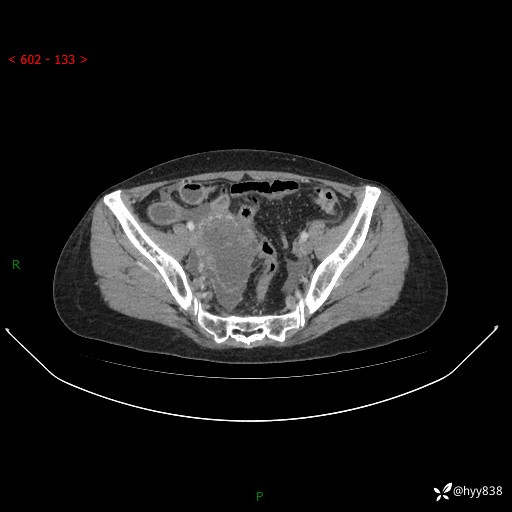

腹盆CT平扫

增强